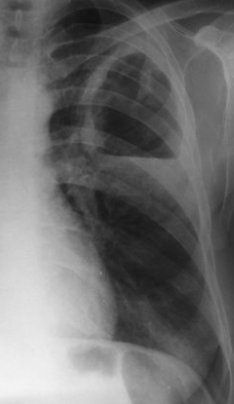

Rx toracică, incidență P-A (centrată pe hemitoracele drept)

DESCRIERE:

în 1/3 sup. a hemitoracelui drept → opacitate de formă triunghiulară, intensitate medie-mare, omogenă

caracter retractil → tracționează traheea și mediastinul de partea afectată + retracția scizurii orizontale (aspect concav)

adenopatii hilare

pahipleurită diafragmatică → îngroșarea pleurei + tracțiuni fibroase

DX: atelectazie prin NBP central endobronșic (pe bronhia lobară sup. dr.)

DD: pneumonie lobară - nu are caracter retractil, prezintă bronhogramă aerică